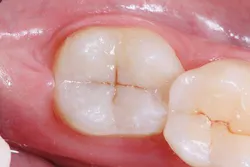

A 26-year-old patient visited a private office for a regular dental checkup. The clinical evaluation showed a No. 18 Class I composite restoration with marginal leakage and infiltration on the distal side of the cavity (figure 1). The surface of the restoration was irregular and lacked dental anatomy. Due to the patient’s esthetic needs and the remaining amount of natural tooth structure, composite filling was selected for the restoration.

The surface anatomy of the restoration was also compromised.